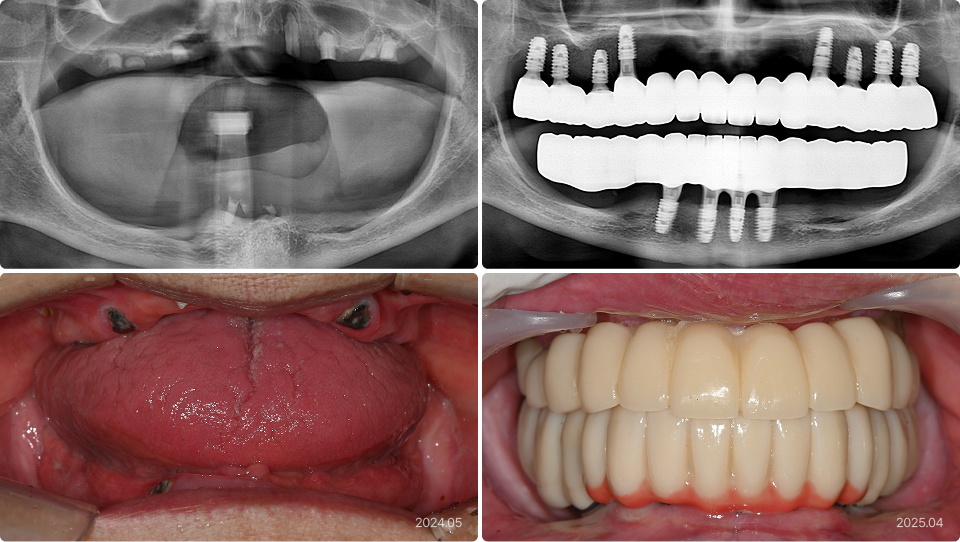

All-4-U 임플란트 치료 사례

93세, 남

“다른 치과에서 임플란트 틀니 했다가 실패했어요.

틀니는 싫고, 나이가 많은데 임플란트가 가능할까요?”

치료 전

치료 후

• 임플란트 틀니 실패로 인한 걱정

• 고정성 보철을 원하지만 고령으로 전신적, 수술적 부담

• 기존 임플란트 제거 및 단 4개 임플란트 식립으로 부담 최소화

• 전체 12개 치아를 연결하는 고정성 보철로 기능 및 심미 회복